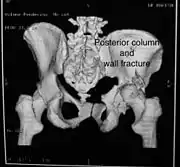

Posterior column and wall fracture as seen on 3D CT

Posterior column and wall fixed using screws and plates